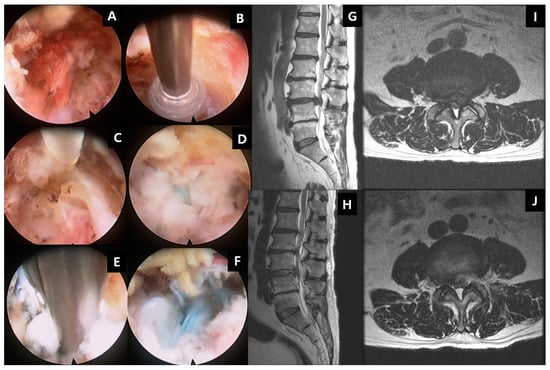

11.4. Recent Development of Endoscopic Spine Surgery and Its Role in Degenerative Disc Diseases